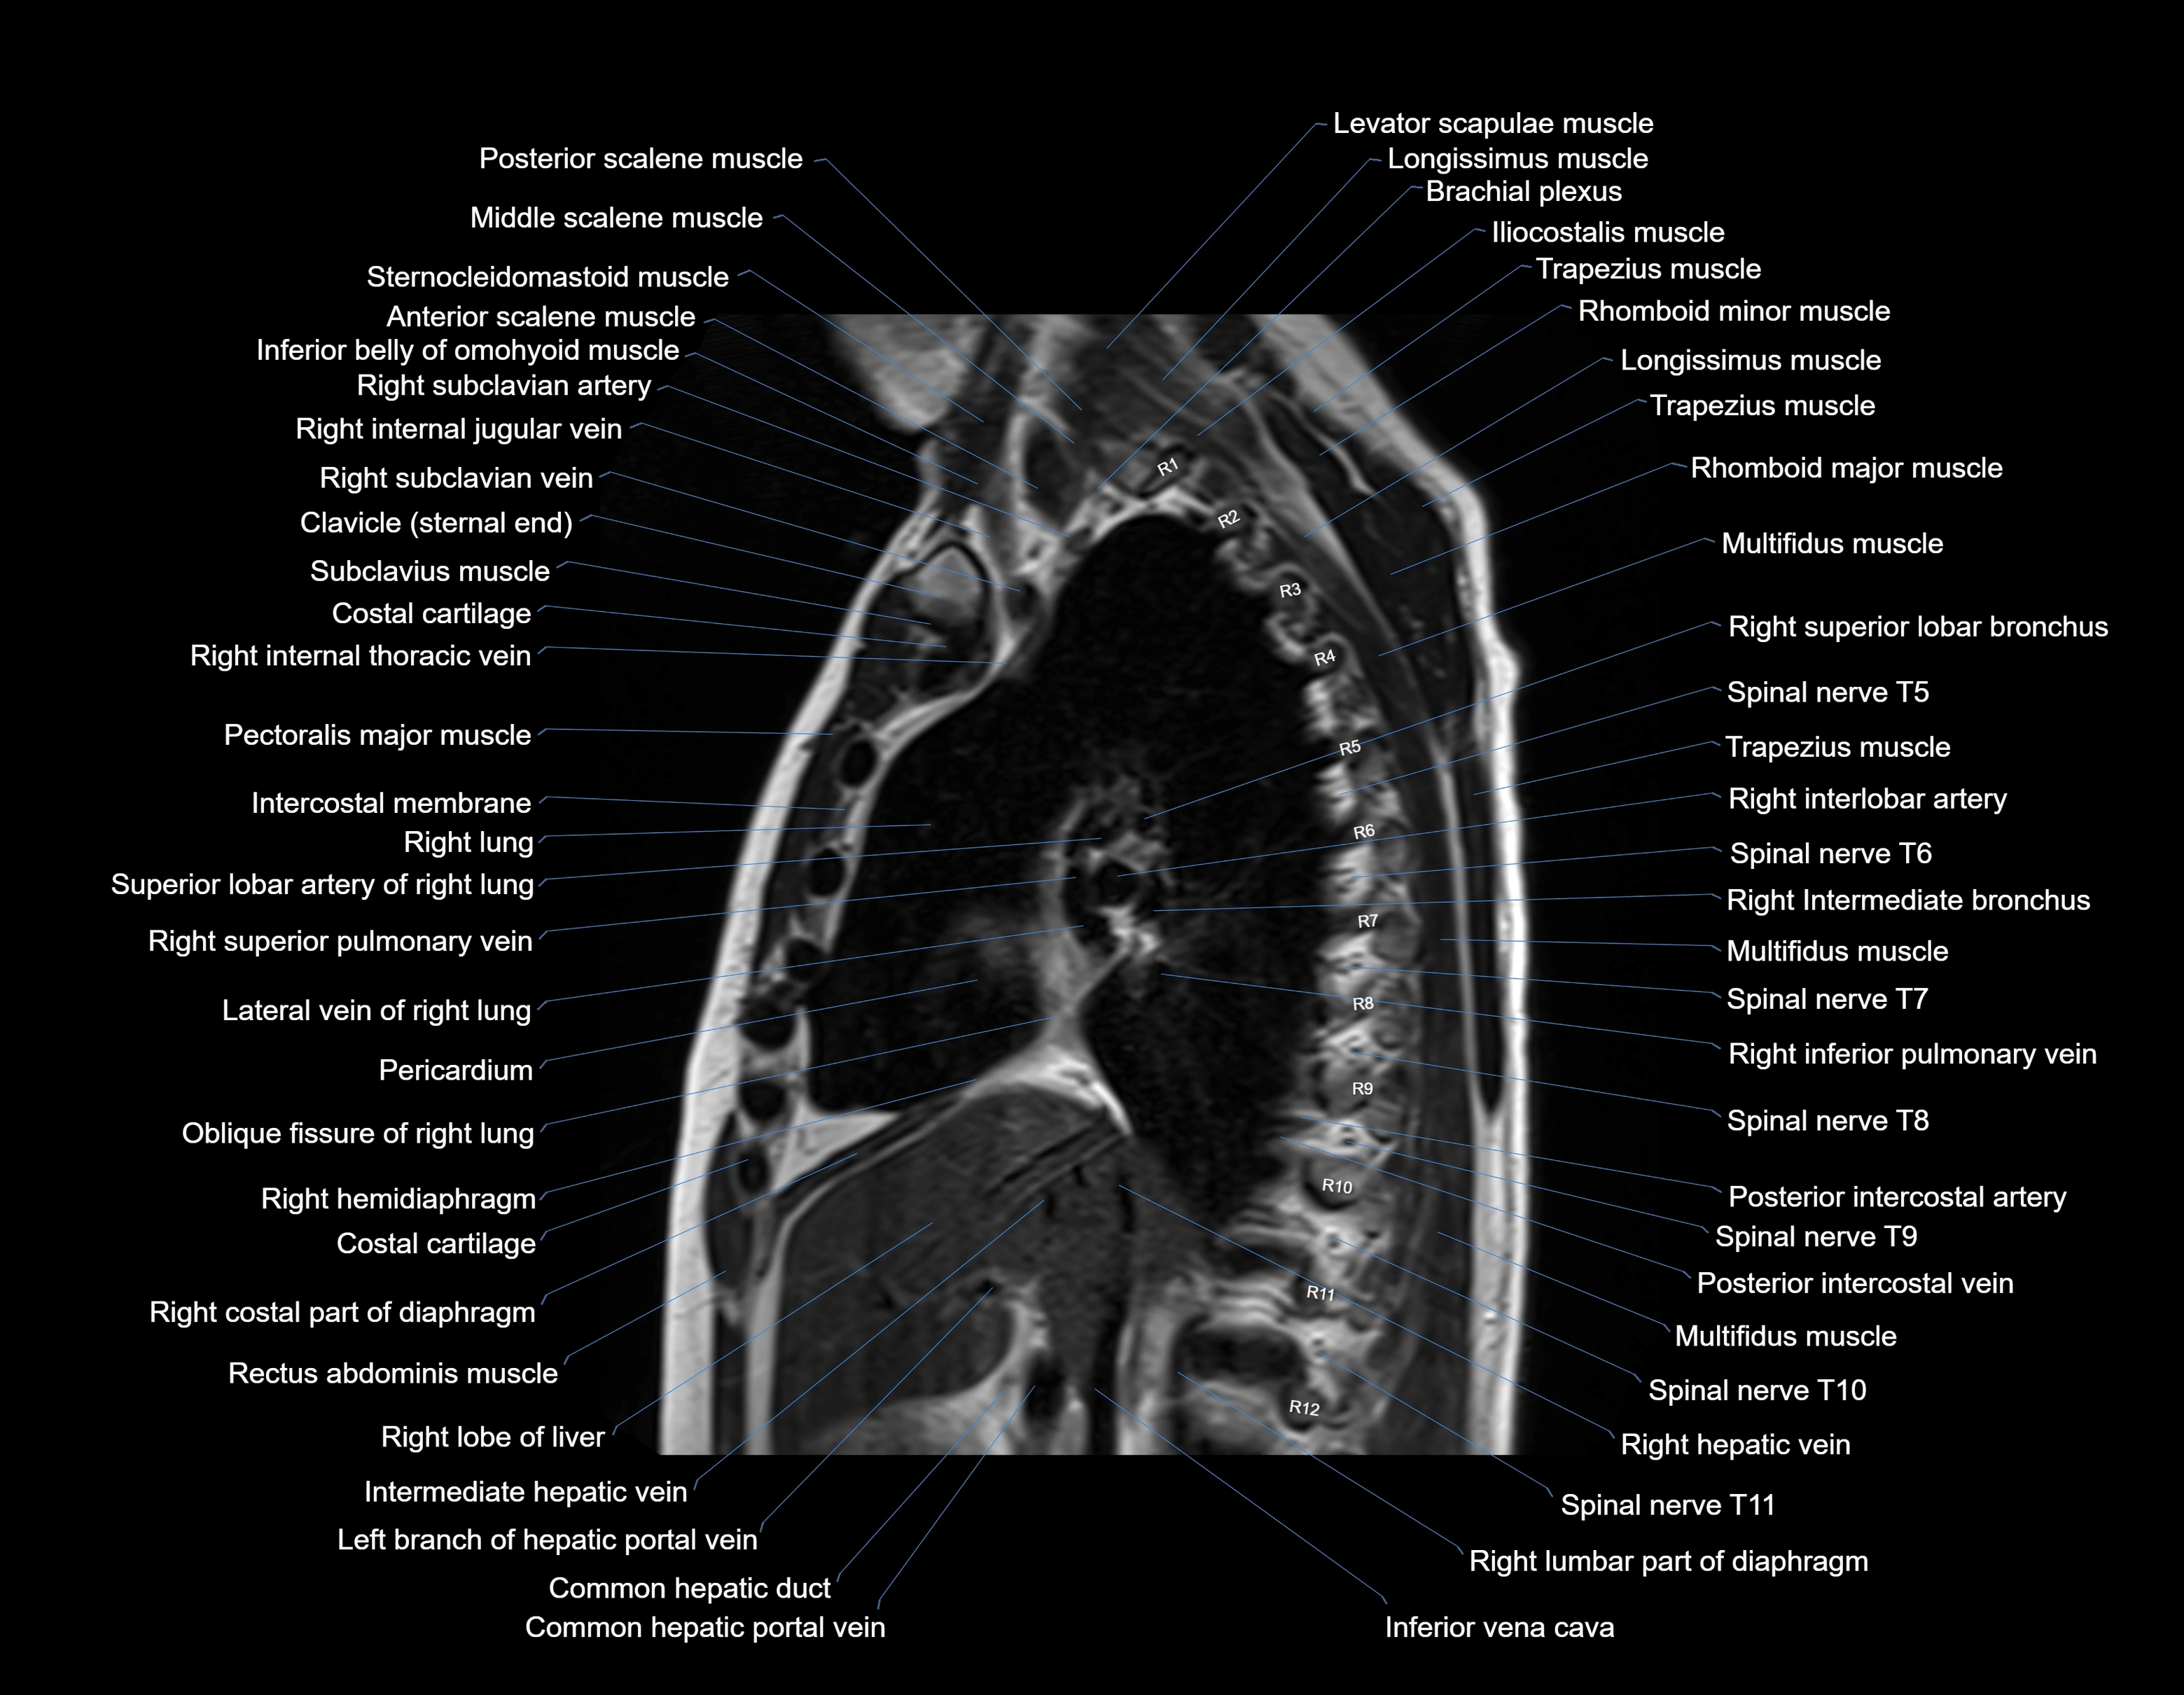

MRI images